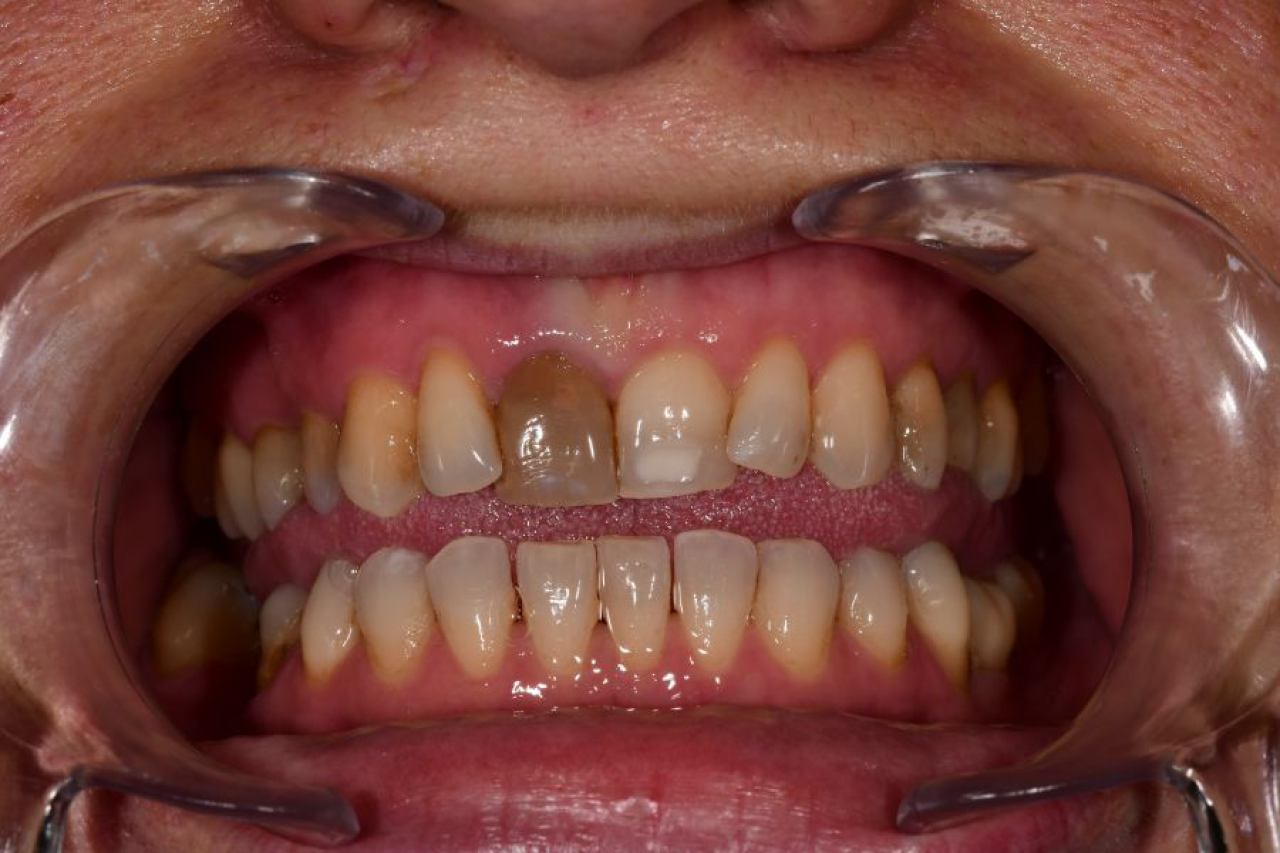

Estetska dentalna medicina

Izbjeljivanje zubi i zubne ljuskice zaštitni su znak Hollywoodskog osmijeha. Izbjeljivanje nije štetno za zube i ne oštećuje caklinu.

Ukoliko niste zadovoljni svojim osmijehom tu je DSD ili Digital Smile Design kojim u okvirima naših mogućnosti ispunjavamo vaše želje „Hollywood smile" ljuskicama, minimalno invanzivnim preparacijama zuba.

Marković Dental Clinic uvijek na prvom mjestu ima zdravlje zubi i zadovoljstvo svakog pacijenta. Koristimo najmoderniji software gdje je pacijentu moguće virtualno prikazati nove zube te kasnije kreirati novi osmijeh protetskim radom, ljuskicama, krunicama ili mostovima.